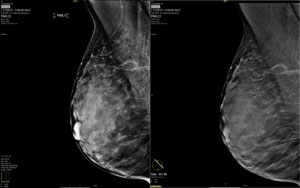

ROCHESTER, N.Y., July 29 — Grey Bruce Health Services’ regional hospital in Owen Sound, Canada, uses Carestream’s Vue PACS and Vue Mammo workstations as part of its breast imaging program that includes Carestream’s digital breast tomosynthesis (DBT) module, full-field digital mammography, breast ultrasound, breast MRI, stereotactic biopsies and screening mammograms.

Breast Tomosynthesis “DBT is becoming the preferred technology for diagnostic exams of patients who are called back due to areas of concern in a screening exam. This technology provides enhanced visualization of breast nodules and lesions, which helps our radiologists make a more confident diagnosis,” said Dr. Scott Thomson, Chief Mammographic Radiologist, Grey Bruce Health Services. “Carestream’s fully featured DBT module is easy to use and offers reading times of one minute to one and a half minutes for a single breast exam.”

The Web-based CARESTREAM Vue Mammo Workstation supports a single, fully featured desktop that enables streamlined reading of all breast imaging procedures as well as delivering advanced 3D breast tomosynthesis tools. The DBT module can display exams side-by-side with other types of mammography procedures, and allows viewing of DBT exams in cine mode or by scrolling through images. Comparison tools enable radiologists to use personalized hanging protocols for DBT exams along with other procedures.